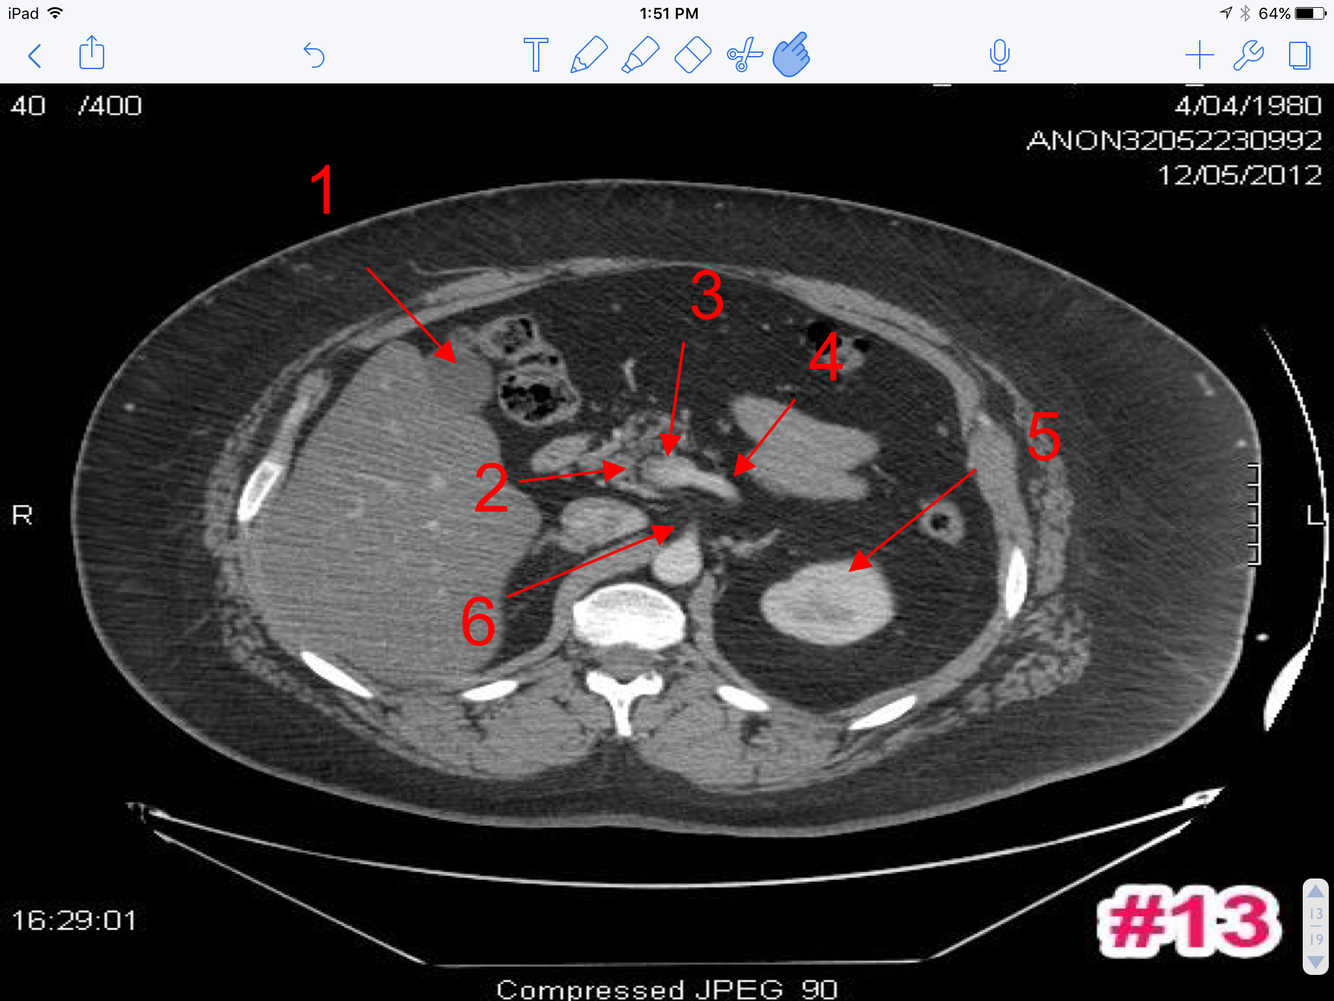

14

Q

A

1. Rt. renal A

2. Lt. renal V

3. Superior mesenteric A

4. Superior mesenteric V

5. Transverse colon

6. Inferior Vena Cava

7. Abdominal Aorta